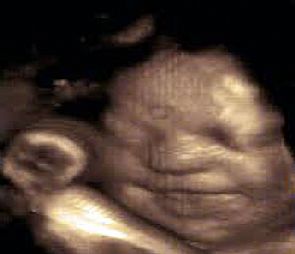

صورة | جنين يبتسم في بطن أمه قبل ولادته بأسابيع

كشفت مجموعة من الصور رباعية الأبعاد '4D'، والتي سلطت الضوء على تعبيرات وجوه مجموعة الأجنة قبل حدوث الولادة بفترات تصل إلى 16 أسبوعا، أن الجنين يتمرن على الابتسامة داخل رحم أمه استعدادا للقاء أبويه، وفقا لفريق من العلماء والباحثين بجامعة 'درهام' البريطانية.

وأشار علماء بالجامعة إلى مفاجأة كبيرة هى الأولى من نوعها على الإطلاق، حيث كشفوا أن الجنين يتمرن على الابتسامة داخل رحم أمه استعداداً للقاء أبويه.

وعلق علماء النفس على تلك الصور غير المسبوقة، مشيرين إلى أن الأجنة تتدرب وتمارس كيفية التعبير عن مشاعرها، وخاصة أنهم على موعد قريب للقاء الأب والأم عقب الولادة مباشرة، وأثبتوا أن قدرات الطفل العقلية على إظهار عواطفه ومشاعره تتطور فى وقت مبكر جداً من حياته، وهو ما يعد أمراً مثيراً للغاية.

يذكر أنه تم التقاط هذه الصور رباعية الأبعاد باستخدام أشعة الموجات فوق الصوتية لحوالى 15 جنينا، تتراوح أعمارهم ما بين 24 إلى 36 أسبوعاً من بداية الحمل.